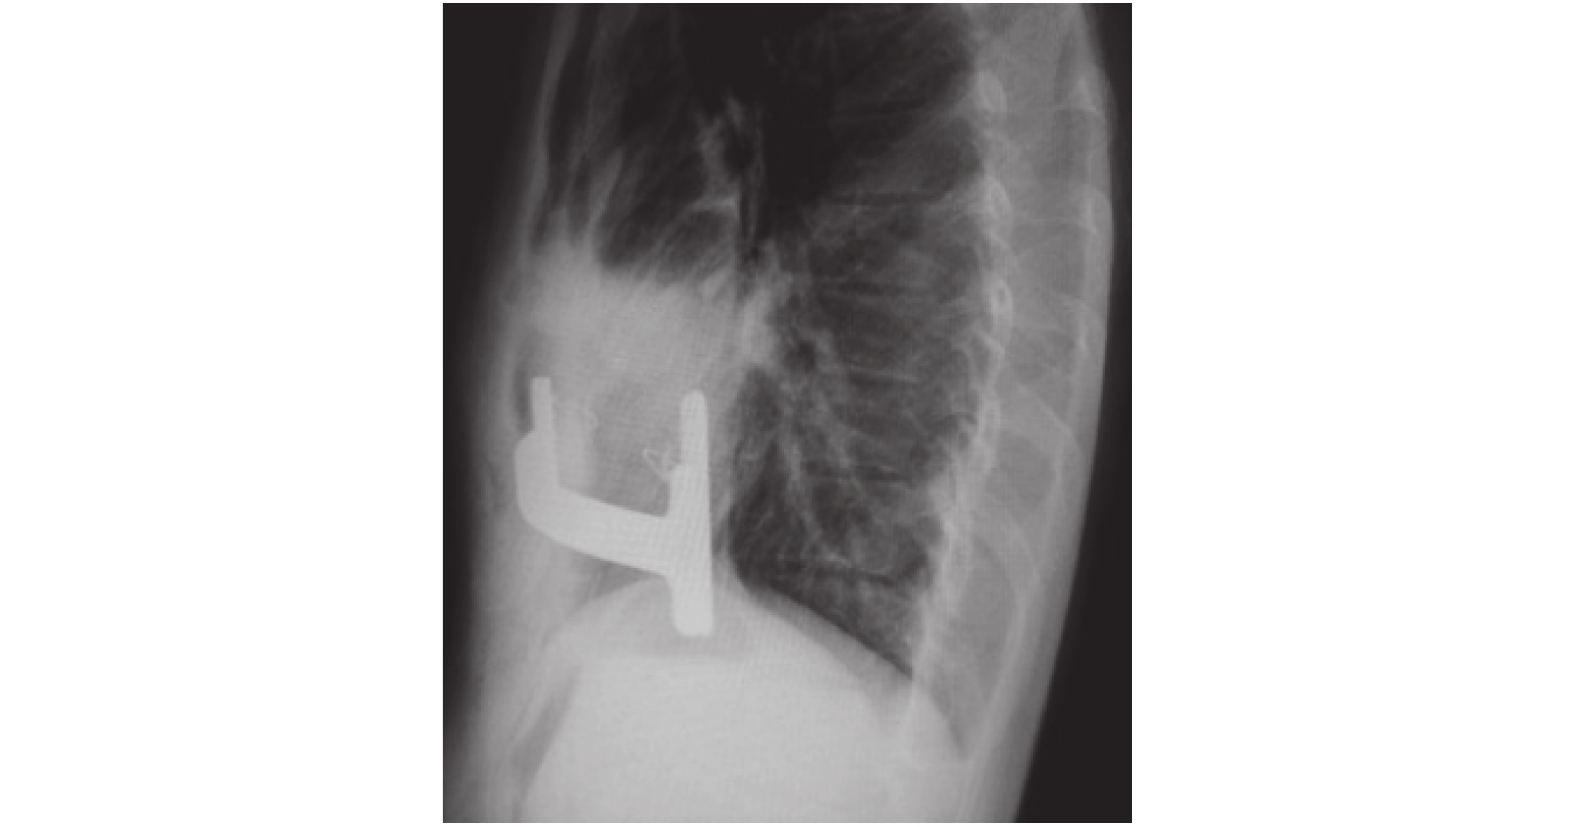

氣管插管靜脈復合麻醉,平臥位。根據患者前胸凹陷的范圍、面積及最低點,確定手術切口及需加強的肋間,切口通常位于雙側腋前線腋中線間,長約 2.5 cm,沿肋骨骨膜外間隙向胸骨方向分離至胸廓最高點,雙側最高點與前胸凹陷最低點位于同一直線。右側腋中后線第 7 或 8 肋間置入胸腔鏡。胸腔粘連嚴重者加行劍突下切口,長 3~5 cm,經該切口分離胸骨后粘連至右側胸腔或雙側胸腔打開胸骨后通道。手指從胸骨后上抬胸骨,如胸骨下沉力量大可切斷胸骨下段左右肋軟骨各 1~2 根松解。為固定鋼板,應用鋼絲跨雙側上下 1~2 根肋骨。用帶引導頭的鋼板組合從右胸切口沿肋骨骨膜外間隙從最高點肋間進右胸,從胸廓最低點穿過胸骨后心包前的間隙,從左側最高點肋間穿出胸腔,沿左胸間隙沿肋骨骨膜外間隙從左胸切口引出鋼板引導頭,胸壁塑形后卸引導頭上固定片(圖 4)。跨肋骨的鋼絲穿矯形鋼板的孔固定鋼板。術后右胸腔排氣后縫合切口。術后胸廓形態立即改善(圖 5、圖 6)。